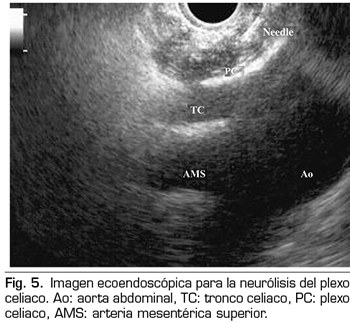

Figura 5